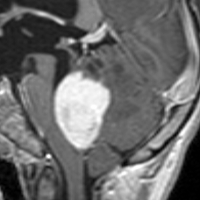

20代女性に偶然発見された視床下部(第3脳室)腫瘍です,T1低信号,T2で高信号,右側のガドリニウム造影では全く増強されません。毛様細胞性星細胞腫と診断できます。眼科での視野検査で視野欠損はありませんでした。生検術もなにもせず経過をみました。

左が初診時,右が5年後のMRI画像です。腫瘍の大きさは全く同じです。このような腫瘍はしばしば経験します。慌てて生検術や開頭手術など計画しないで,画像診断をしっかりすることが大切です。